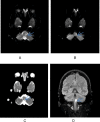

A 19-year-old man was admitted with a 2-week history of continuous cough along with a day history of acute onset unsteadiness and hiccups. Given the current pandemic, he was initially suspected to have COVID-19, however he tested negative on two occasions. Subsequent brain magnetic resonance imaging (MRI)confirmed a small left acute and subacute lateral medullary infarction with chest X-ray suggesting aspiration pneumonia with right lower lobe collapse. This is a distinctive case of posterior circulation stroke presenting with a new continuous cough in this era of COVID-19 pandemic. We anticipate based on MRI findings that his persistent cough was likely due to silent aspiration from dysphagia because of the subacute medullary infarction. It is therefore imperative that healthcare workers evaluate people who present with new continuous cough thoroughly to exclude any other sinister pathology. We should also be familiar with the possible presentations of posterior circulation stroke in this pandemic era.